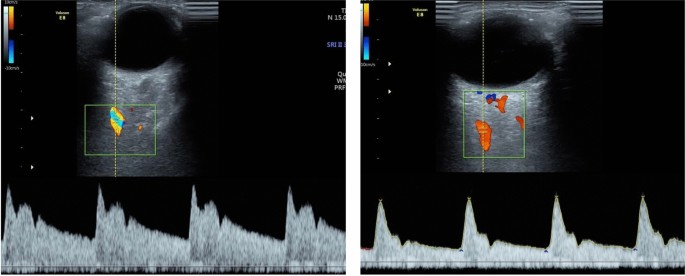

The elevation of PI, P2, and PR modified the wave morphology, with an increase in the hump in relation to the velocity waveform patterns found in the CG (Fig. 2). There were no differences in the other OA Doppler indexes (IR, PVS, and EDV) between the SG and the CG. There was significantly higher impedance in the MCA in the female SG compared with the CG, represented by higher RI and PI and lower EDV. Other velocities (PVS, EDV, and VM) were not different between the two groups. Therefore, there were antagonistic response patterns of the OA and the MCA in the female chronic smokers. Although age had an influence on OA values, cigarette use is an independent modifying factor in wave morphology, since p remains significant even with correction of the covariate age and use of oral contraceptives.

Ophthalmic artery Doppler demonstrating different wave morphology with elevation of the second peak systolic velocity P2 and peak ratio (on the left) compared to Doppler waveform with low P2 and peak ratio in non-smokers group (on the right).